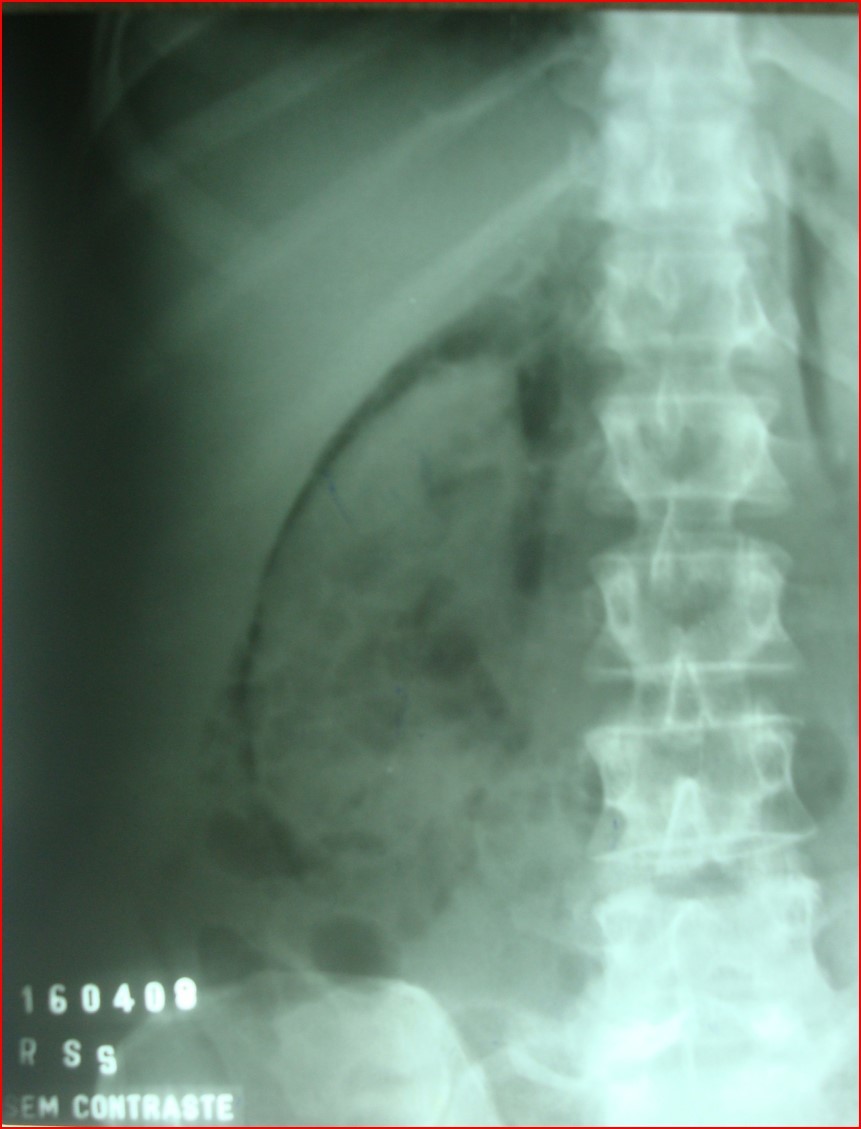

NESTA RADIOGRAFIA SIMPLES DO ABDOME, VC OBSERVA UM VELAMENTO DIFUSO DO HEMIABDOME ESQUERDO, COM EFEITO COMPRESSIVO NAS ALÇAS INTESTINAIS PREENCHIDAS POR GASES , QUE SE ENCONTRAM DESLOCADAS .

TUMOR MALIGNO MAIS FREQUENTE NA INFÂNCIA.ASSINTOMÁTICO ATÉ QUE A MÃE PERCEBE A MASSA ABDOMINAL.

A patologia renal mais comum em criança com massa palpável é?

Tumor de Wilms

MASSAS ABDOMINAIS EM PEDIATRIA :

RECÉM-NATO : HIDRONEFROSE POR ESTENOSE DA JUP

2 A 5 ANOS : TUMOR DE WILMS ou NEFROBLASTOMA (renal) ou NEUROBLASTOMA (adrenal).